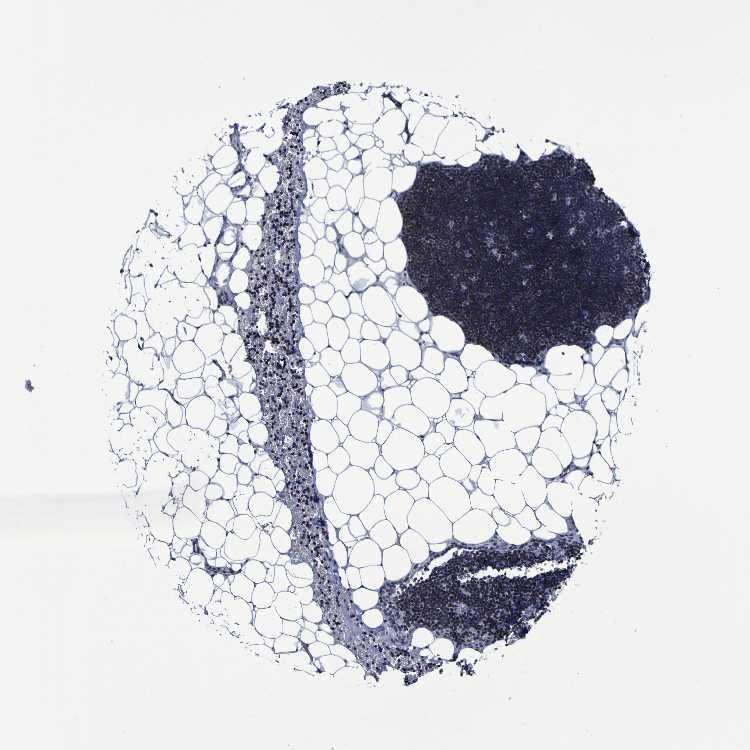

LYMPH NODE - Antibody stainingi

Antibody staining in the annotated cell types in the current human tissue is reported as not detected, low, medium, or high, based on conventional immunohistochemistry profiling in selected tissues. This score is based on the combination of the staining intensity and fraction of stained cells.

Each image is clickable and will lead to virtual microscopy that enables deeper exploration of all samples and also displays staining intensity scores, fraction scores and subcellular localization as well as patient and tissue information for each sample.

Antibody CAB013265

Germinal center cells Low

Non-germinal center cells Low